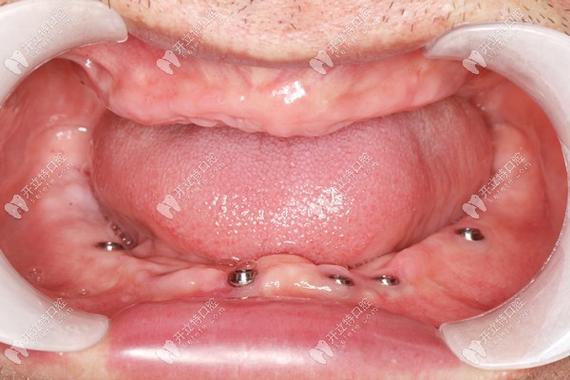

- 技术领先: 拥有最先进的设备和技术(如数字化导板种植、即刻种植、微创种植、All-on-4/6等复杂种植技术)。

- 数字化技术应用: 术前CBCT检查、数字化导板设计、口内扫描等能提高种植的精准度和安全性,减少创伤,缩短时间,了解医院/机构是否具备这些条件。